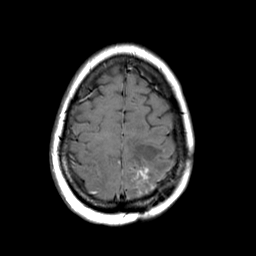

MR Study #3 -- Slice #42